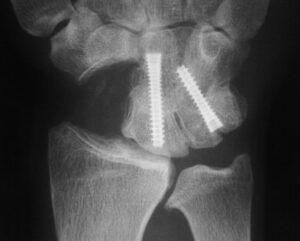

Radiografie van pols na scafoidectomie en 4 corner fusie

- 4 Corner fusie: het weghalen van één botje in de handwortel (het scafoid) en het doen vastgroeien van 2 paar handwortelbeenderen. Dit zorgt voor een voorspelbare afname van de pijn, en de pols verliest ongeveer 50% beweeglijkheid ten opzichte van een gezonde pols, de lengte van de pols wordt door deze ingreep beter behouden en er is dus theoretisch minder risico op krachtsverlies. Deze ingreep is ingewikkelder dan een proximale rij resectie en heeft iets meer risico op complicaties. (Het niet vastgroeien van de botjes, het storen van het osteosynthesemateriaal)